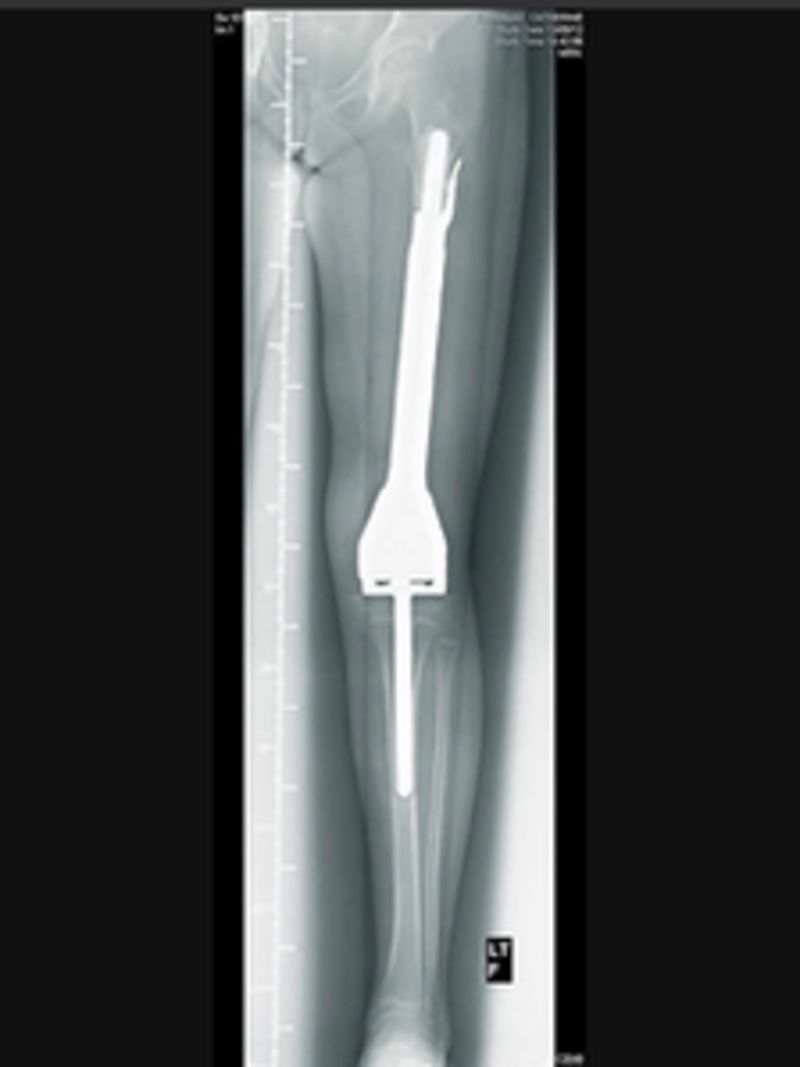

Can You Run With A Titanium Rod In Your Leg. I was curious if anyone out there has a similar experience? Infection, loosening, and fractures are. I have a chronic condition that limits my mobility. i would suggest to find what you can do in the meantime. This article will review physical therapy exercises for a femur fracture, a recovery timeline, and tips for getting started. Or can you play sports with a plate and screws in your arm or leg? I discuss those questions in my latest ask dr. You might need this procedure to treat your broken shinbone (tibia) or your fibula. open reduction and internal fixation (orif) is a type of surgery used to stabilize and heal a broken bone. Do you need to have it removed?  — physical therapy is often needed for a femur fracture to heal properly. plates, screws, rods and pins can all be used, depending on what type of fracture it is. Usually, the rod is made of titanium and they come in different lengths and diameters to fit patients of different ages and heights. What happens to that hardware? Beside it is the fibula.

This article will review physical therapy exercises for a femur fracture, a recovery timeline, and tips for getting started.  — physical therapy is often needed for a femur fracture to heal properly. i broke both my tibia and fibula this past april. I have a chronic condition that limits my mobility. Do you need to have it removed? Surgery was done placing a rod in my leg. A metal rod in your leg can cause pain and discomfort in some cases. Usually, the rod is made of titanium and they come in different lengths and diameters to fit patients of different ages and heights. i would suggest to find what you can do in the meantime. Or can you play sports with a plate and screws in your arm or leg?

Can You Run With A Titanium Rod In Your Leg The tibia, or shinbone, is the larger bone in your lower leg. plates, screws, rods and pins can all be used, depending on what type of fracture it is. You might need this procedure to treat your broken shinbone (tibia) or your fibula. What happens to that hardware? open reduction and internal fixation (orif) is a type of surgery used to stabilize and heal a broken bone.  — physical therapy is often needed for a femur fracture to heal properly. Usually, the rod is made of titanium and they come in different lengths and diameters to fit patients of different ages and heights. This will enable you to comfortably bear weight on your injured leg to stand up, walk, go up and down stairs, and exercise. I can't jog or run so i. Do you need to have it removed? i broke both my tibia and fibula this past april. This article will review physical therapy exercises for a femur fracture, a recovery timeline, and tips for getting started. Or can you play sports with a plate and screws in your arm or leg?  — do bones hurt as they heal? The tibia, or shinbone, is the larger bone in your lower leg. A metal rod in your leg can cause pain and discomfort in some cases.